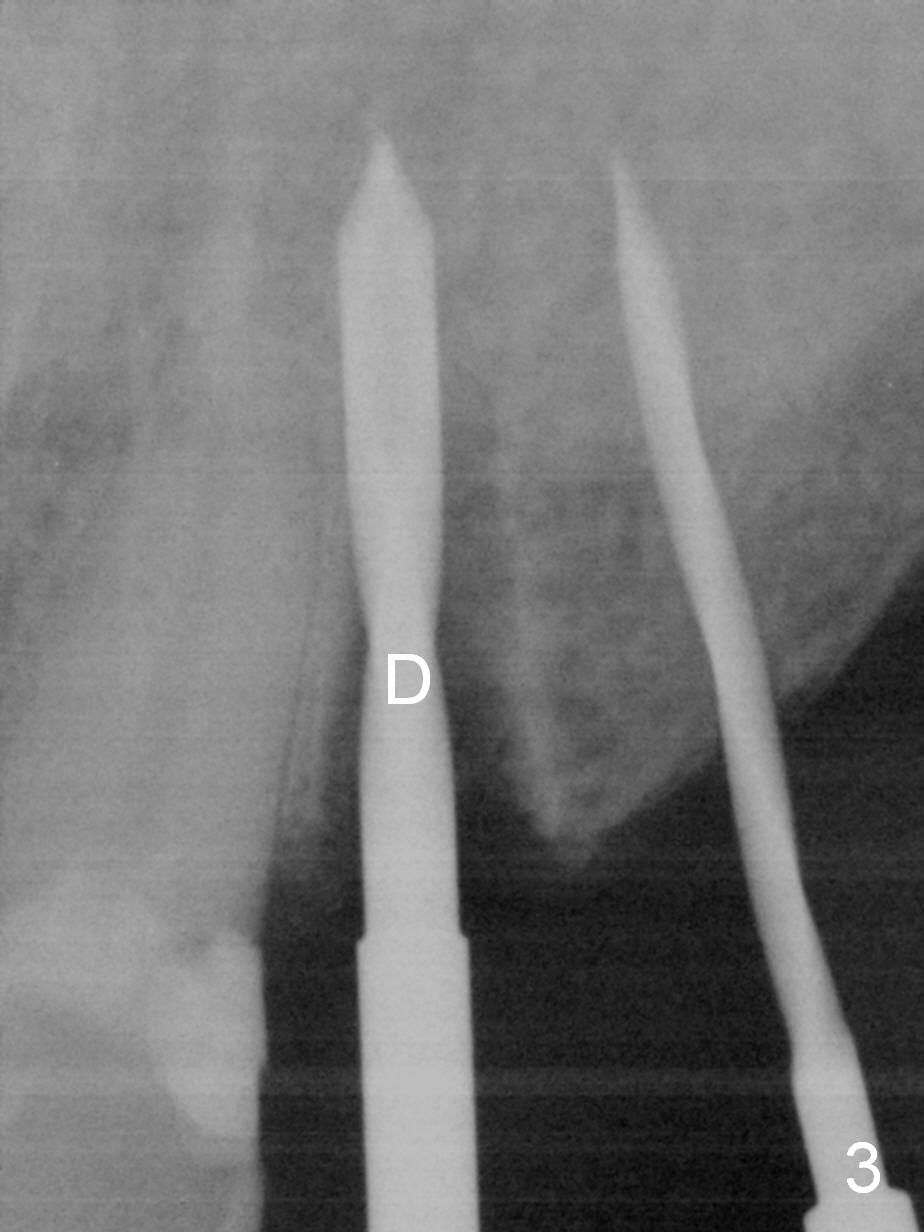

Six months post cementation of implant crown at #10, the tooth #9 becomes symptomatic with buccal apical swelling and tenderness (Fig.1). The implant and the neighboring root are close to each other. Due to extensive restoration and periapical radiolucency at #9 with percussion, root canal therapy begins with placement of calcium hydroxide. The pain reduces by the evening.

How to avoid apparent iatrogenic damage to the neighboring root? Preop PA shows approximation of these roots (Fig.2). Unfortunately the initial osteotomy is too mesial (Fig.3), which is unnoticed. When a 4.5x17 mm implant is placed, there is distal gap (Fig.4 <), while the mesial one is closed.